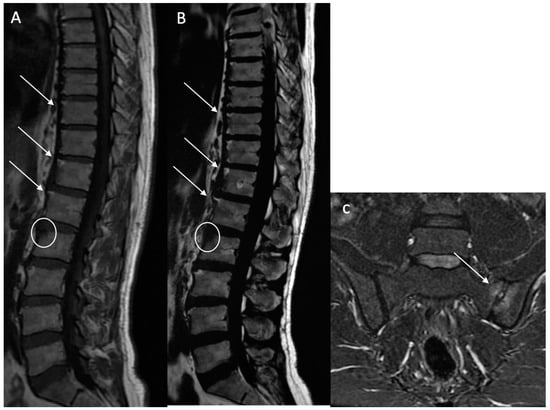

Ankylosis (A): Defined as bony ankylosis with heterotopic bone formation and no discal space on both sequences (Figure 5).

Figure 5. Lumbar vertebral ankylosis with “squared vertebrae” in a 54-year-old patient. A T1w sagittal sequence showing vertebral ankylosis with corporeal vertebral partial bone fusion from T9 to T11 and from T12 to L2 (arrows). The “squared” aspect of the corporeal vertebrae is noted (A). A T2w Dixon (fat) image better showing vertebral ankylosis with corporeal vertebral partial bone fusion (arrows) (B).